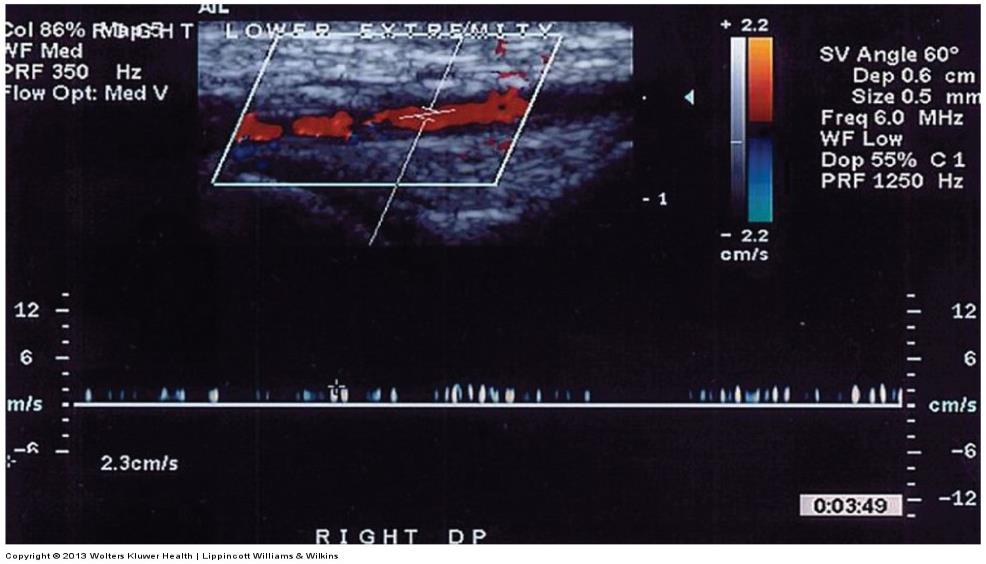

ultrasound image of a very low velocity vessel